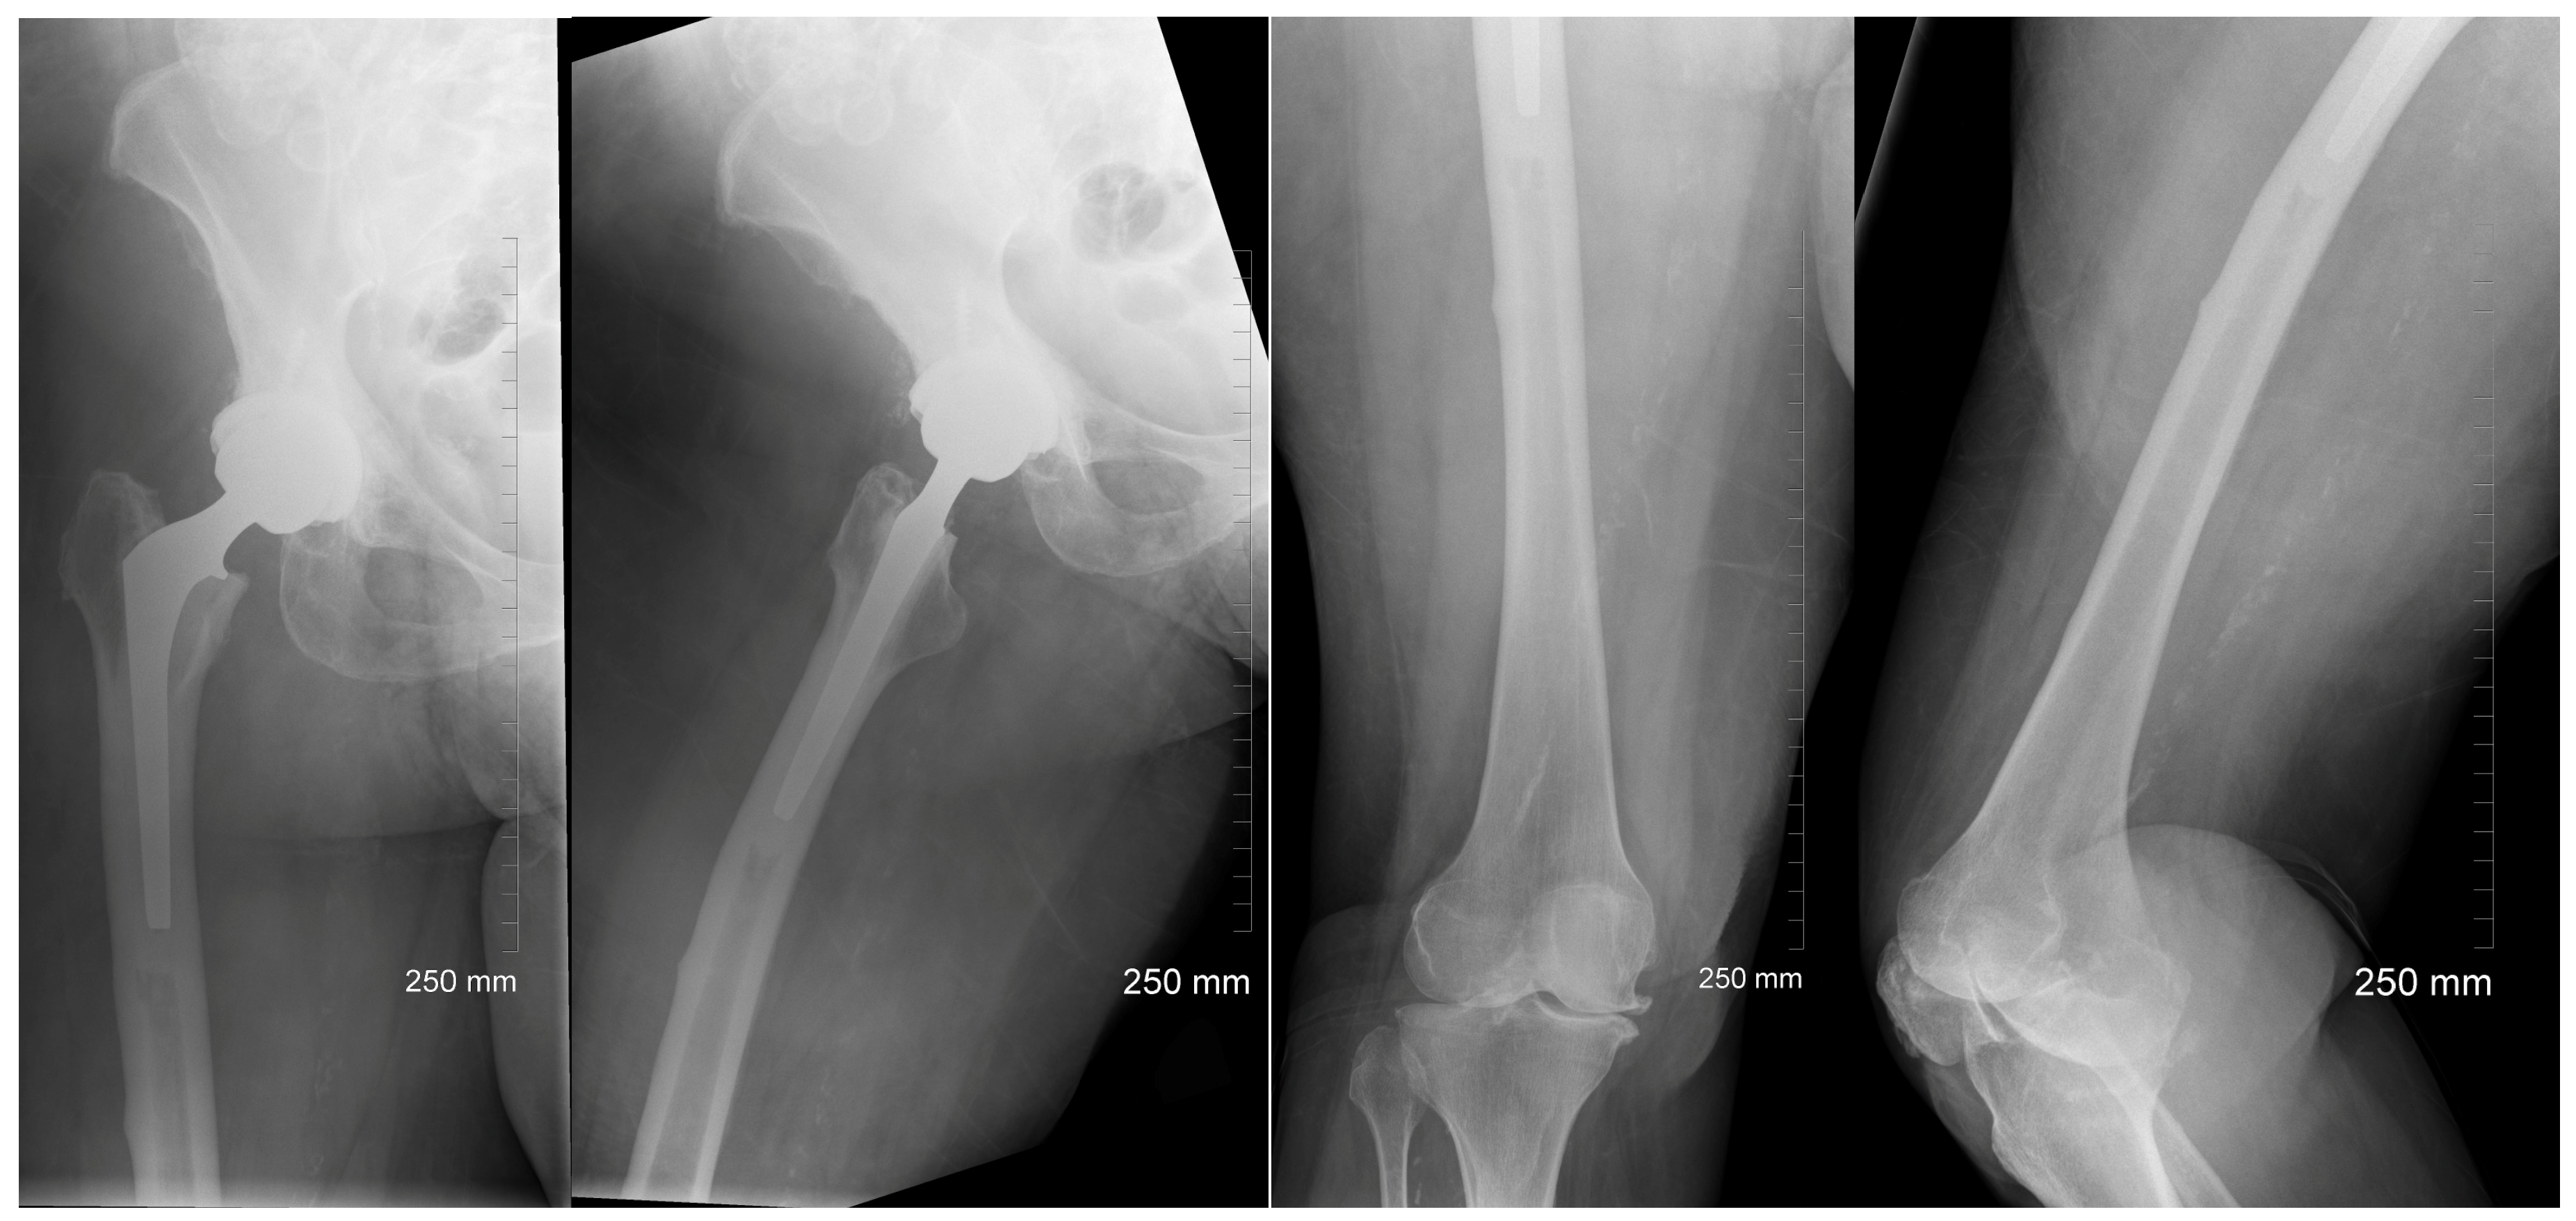

2. Case Description